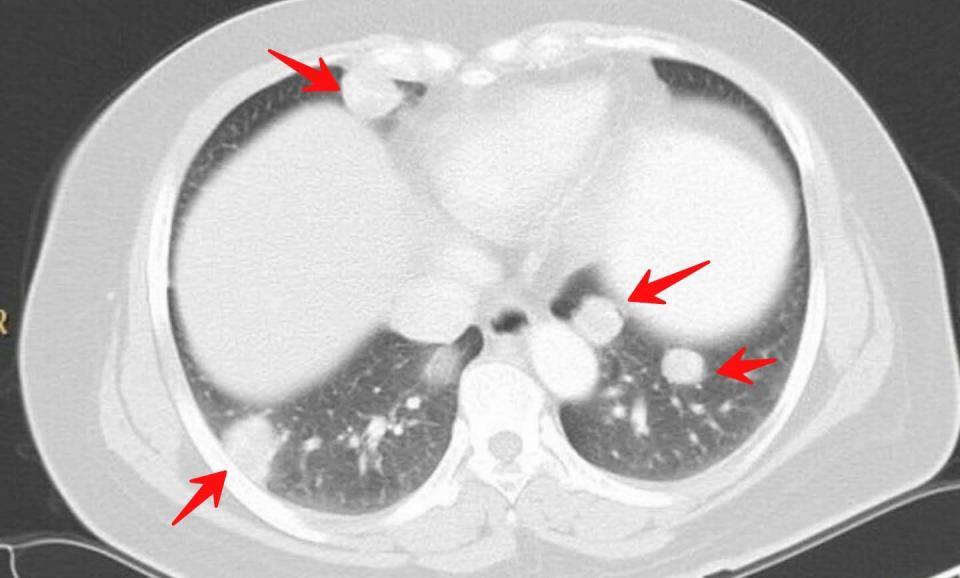

5.下面是一位流产后绒毛膜上皮癌的女性患者,因为咯血发现肺内多发转移瘤:

绒癌对化疗敏感,这位患者后来治愈出院了。